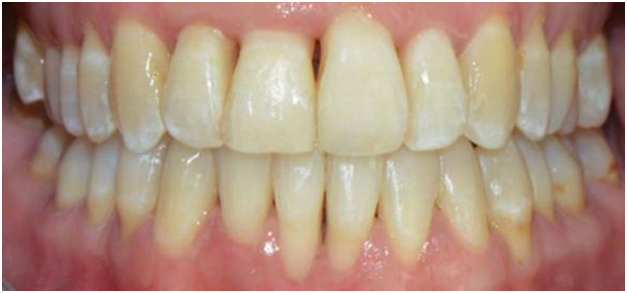

The second case (Figure 3) displays moderately malpositioned mandibular anterior teeth and essentially illustrates the method and apparatus for the restoration of alveolar bone morphology. The patient presented to a FASTBRACES® provider's private practice with a chief complaint of unfavorable esthetic appearance as it relates to moderate alveolar bone hypoplasia or Orthodontosis™ labial to the lingually displaced mandibular incisors roots. This results in a deficiency of alveolar bone labial to the central incisor that demonstrates the gingival recession. The treatment objectives, in this case, are to restore the morphology of alveolar bone around the malpositioned teeth which in turn will allow for new bone to cover the recession.

Figure 3 Before Maxillary and Mandibular Orthodontosis™ and Orthodontitis™ of anterior teeth with localized severe gingival recession, (Courtesy of Dr. Patrick Assal, Lausanne Switzerland).